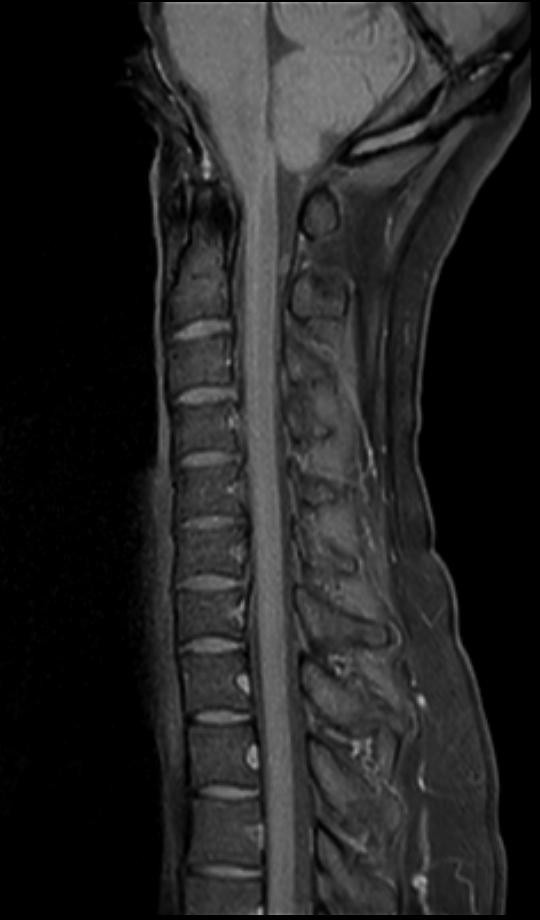

Sagittal T1w mDIXON TSE (Water)

Sagittal T2w mDIXON TSE (Water)